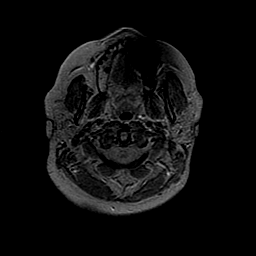

MR Study #2 -- Slice #2

[Home][Help][Clinical][Tour 1][Tour 2][Tour 3] Slice 2